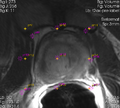

• Loadable module to simplify user-guided interactive segmentation has been developed. The workflow consists of two steps:

• Initialization: user provides B-spline transformation, the fixed and moving fiducial grids are initialized based on the configuration of the B-spline control point grid over the image.

• Adjustment: user can iteratively change the locations of the moving fiducials, and apply deformable registration (Landwarp is wrapped by the module).

• Processing time for the adjustment step is ~10 seconds (3x3x3 grid, 320x320x25 fixed image volume, single-threaded Landwarp, 2.2GHz Intel Core i7)